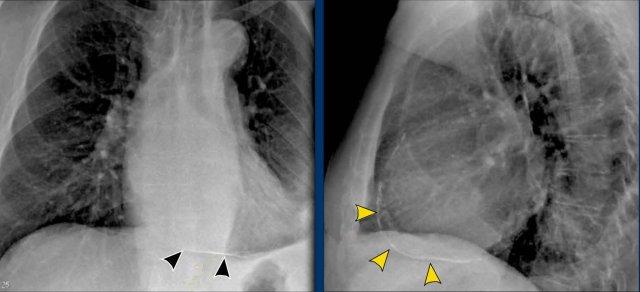

Dịch chuyển đường azygô-thực quản (1) – Thoát vị hoành

Thoát vị hoành (đầu mũi tên) là nguyên nhân phổ biến nhất gây dịch chuyển đường azygô-thực quản quan sát thấy trên phim tư thế thẳng (PA).

Lưu ý hình ảnh khí trong túi thoát vị trên phim tư thế nghiêng (mũi tên đen).

Dịch chuyển đường azygô-thực quản (2) – Hạch to dưới carina

Một nguyên nhân thường gặp gây dịch chuyển đường azygô-thực quản là hạch to dưới carina (trạm 7).

Trên phim X-quang ngực, lưu ý hình ảnh đường azygô-thực quản bị đẩy lên trên ngay dưới carina, phù hợp với hình ảnh hạch bạch huyết dưới carina to (mũi tên đen).

Ngoài ra còn thấy hạch to cạnh khí quản phải, đẩy dải cạnh khí quản phải (mũi tên trắng) và làm lệch khí quản sang trái.